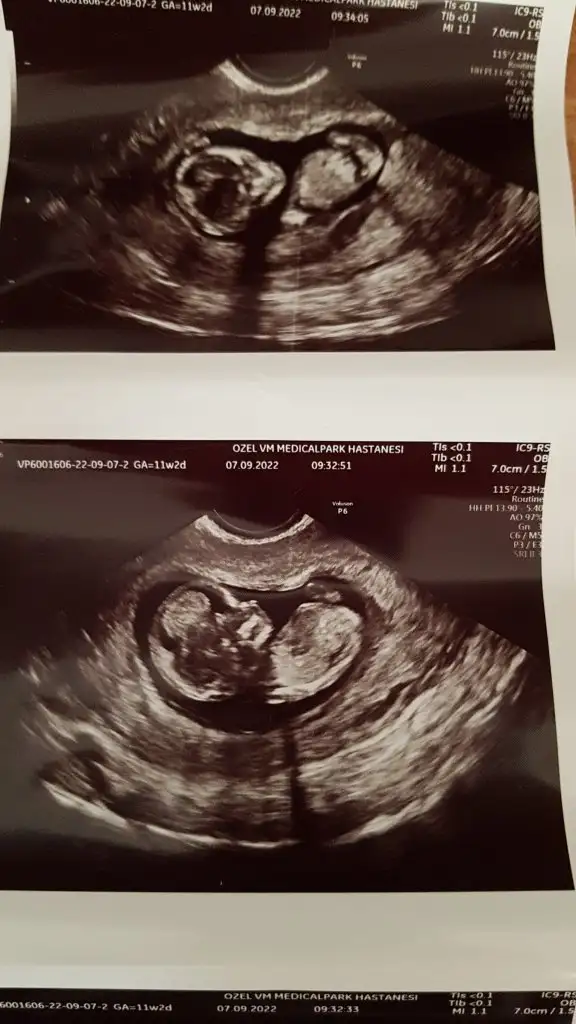

Ne güzel erken söylemiş benim 13. Hafta ama hala net değil beklemedeyim, cinsiyeti kız mıı?Selam kızlar bugün ikili tarama için gittim. Ultrason ölçümünde herşey iyi dedi doktor yaş faktörü kaynaklı kanda yüksek çıkar onu dikkate alıp panik yapma önemli olan benim ölçümüm ve hekim olarak gördüklerimden mutluyum dedi. 1 hafta sonra sonuç çıkacak gel yüzyüze açıklayayım aklında soru kalmasın dedi.icim rahatladı cinsiyetimizi de söylediinşallah hepimizin sonucları güzel çıkar sağlıkla geçirir bu süreci sağlıkla alırız bebislerimizi kucağımiza.

Erkek diye düşünüyorum canımBunlar 11+6 haftadan görüntüler

Kıza benziyor bu pek narin geldi banaSelam kızlar bugün ikili tarama için gittim. Ultrason ölçümünde herşey iyi dedi doktor yaş faktörü kaynaklı kanda yüksek çıkar onu dikkate alıp panik yapma önemli olan benim ölçümüm ve hekim olarak gördüklerimden mutluyum dedi. 1 hafta sonra sonuç çıkacak gel yüzyüze açıklayayım aklında soru kalmasın dedi.icim rahatladı cinsiyetimizi de söylediinşallah hepimizin sonucları güzel çıkar sağlıkla geçirir bu süreci sağlıkla alırız bebislerimizi kucağımiza.